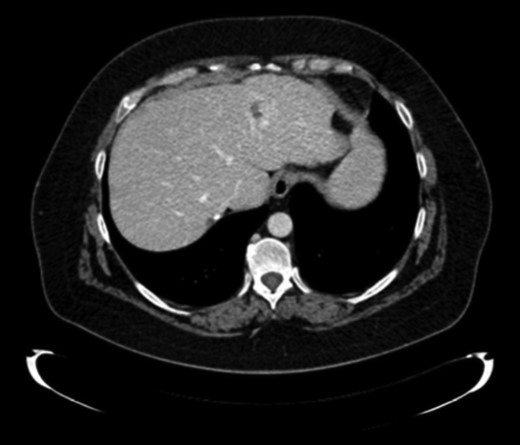

Ten months later, CT revealed two hepatic lesions (segment III of 3 cm and segment VII of 1 cm) (Fig. 2) The biopsy confirmed the original histology of SNUC. Chemotherapy with docetaxel 75 mg/m2, cisplatin 75 mg/m2 and 5 FU 750 mg/m2 every 3 weeks for 3 months was administrated. Because of minimal response was achieved after chemotherapy (Fig. 2) a non-anatomical metastasectomy was performed.

CT scan first relapse. Liver metastases: sIII and sVII 2.2 CT scan after neoadjuvant chemotherapy.